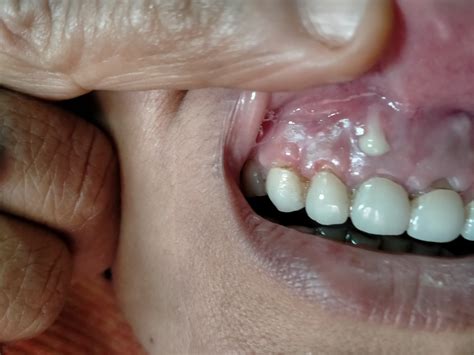

• Torus Palatinus: This is a bony growth that occurs on the roof of the mouth.

Bony growths on gums are often asymptomatic, meaning they do not cause any noticeable symptoms. However, in some cases, individuals may experience:

• Discomfort or pain, especially if the growth is large or interferes with normal oral functions.

• Difficulty chewing or speaking, particularly if the growth is located on the roof of the mouth or near the teeth.

• Visible lumps or bumps on the gums or inside the mouth.

• Visual Examination: The dentist will visually inspect the growth to determine its size, shape, and location.

• X-Rays: Dental X-rays may be taken to assess the extent of the growth and its impact on surrounding structures.

• Biopsy: In some cases, a biopsy may be performed to rule out any malignant conditions, although this is rare for benign bony growths.

• Surgical Removal: In cases where the growth is large or causes discomfort, surgical removal may be recommended. This procedure is typically performed under local anesthesia and involves the removal of the bony growth.